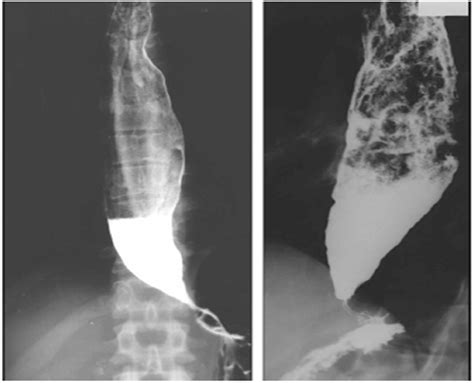

• Barium swallow test: This imaging study uses a contrast agent to visualize the esophagus and identify any abnormalities.